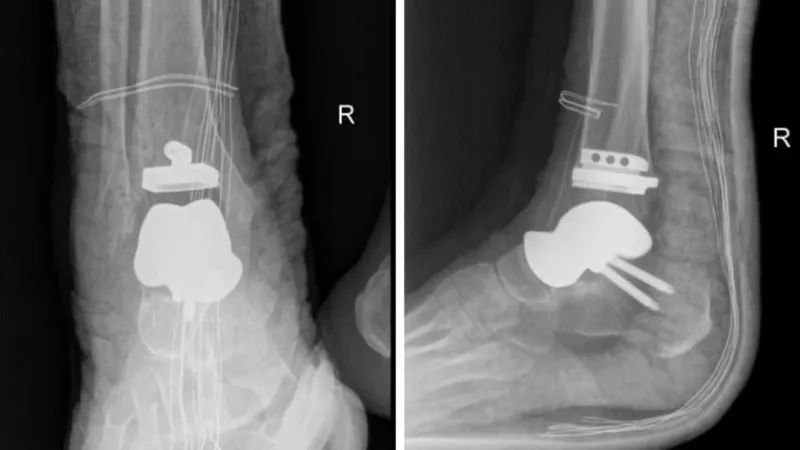

术后X线片。